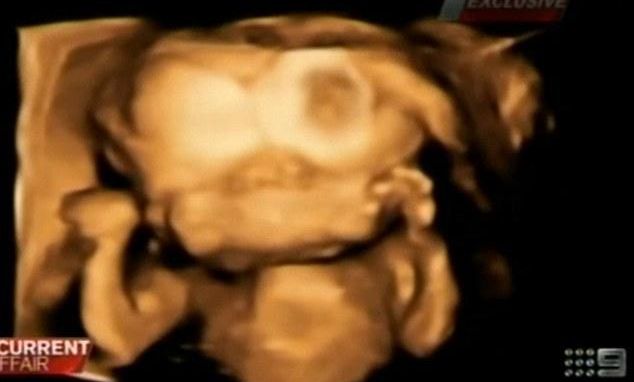

11 feb. 2014, 20:49LifestyleCe au hotărât după ce au aflat că vor fi părinţii unui copil cu două feţe şi două creiere